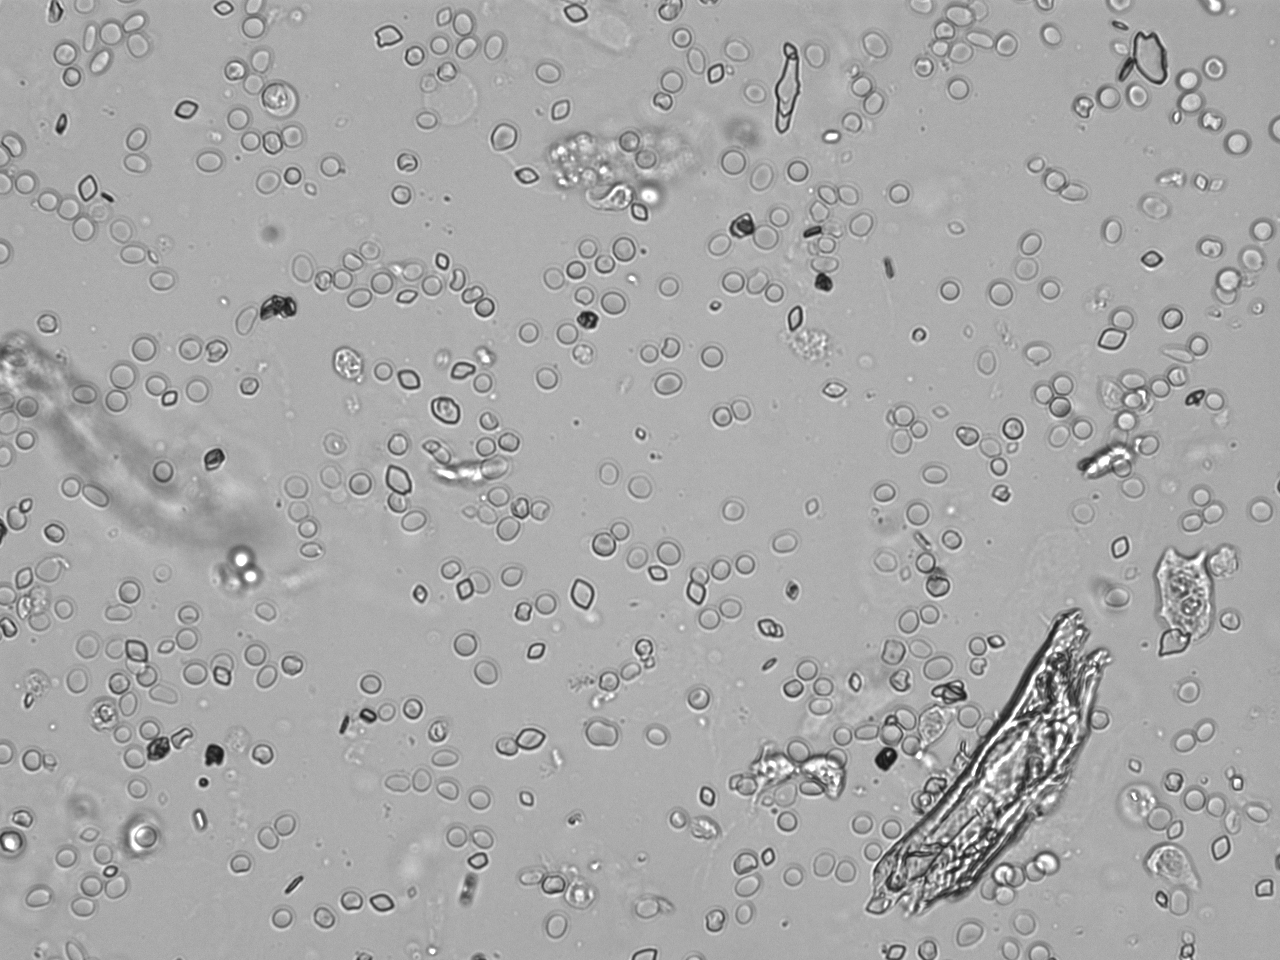

Urin-Feature: Harnskristalle_Rhomboid